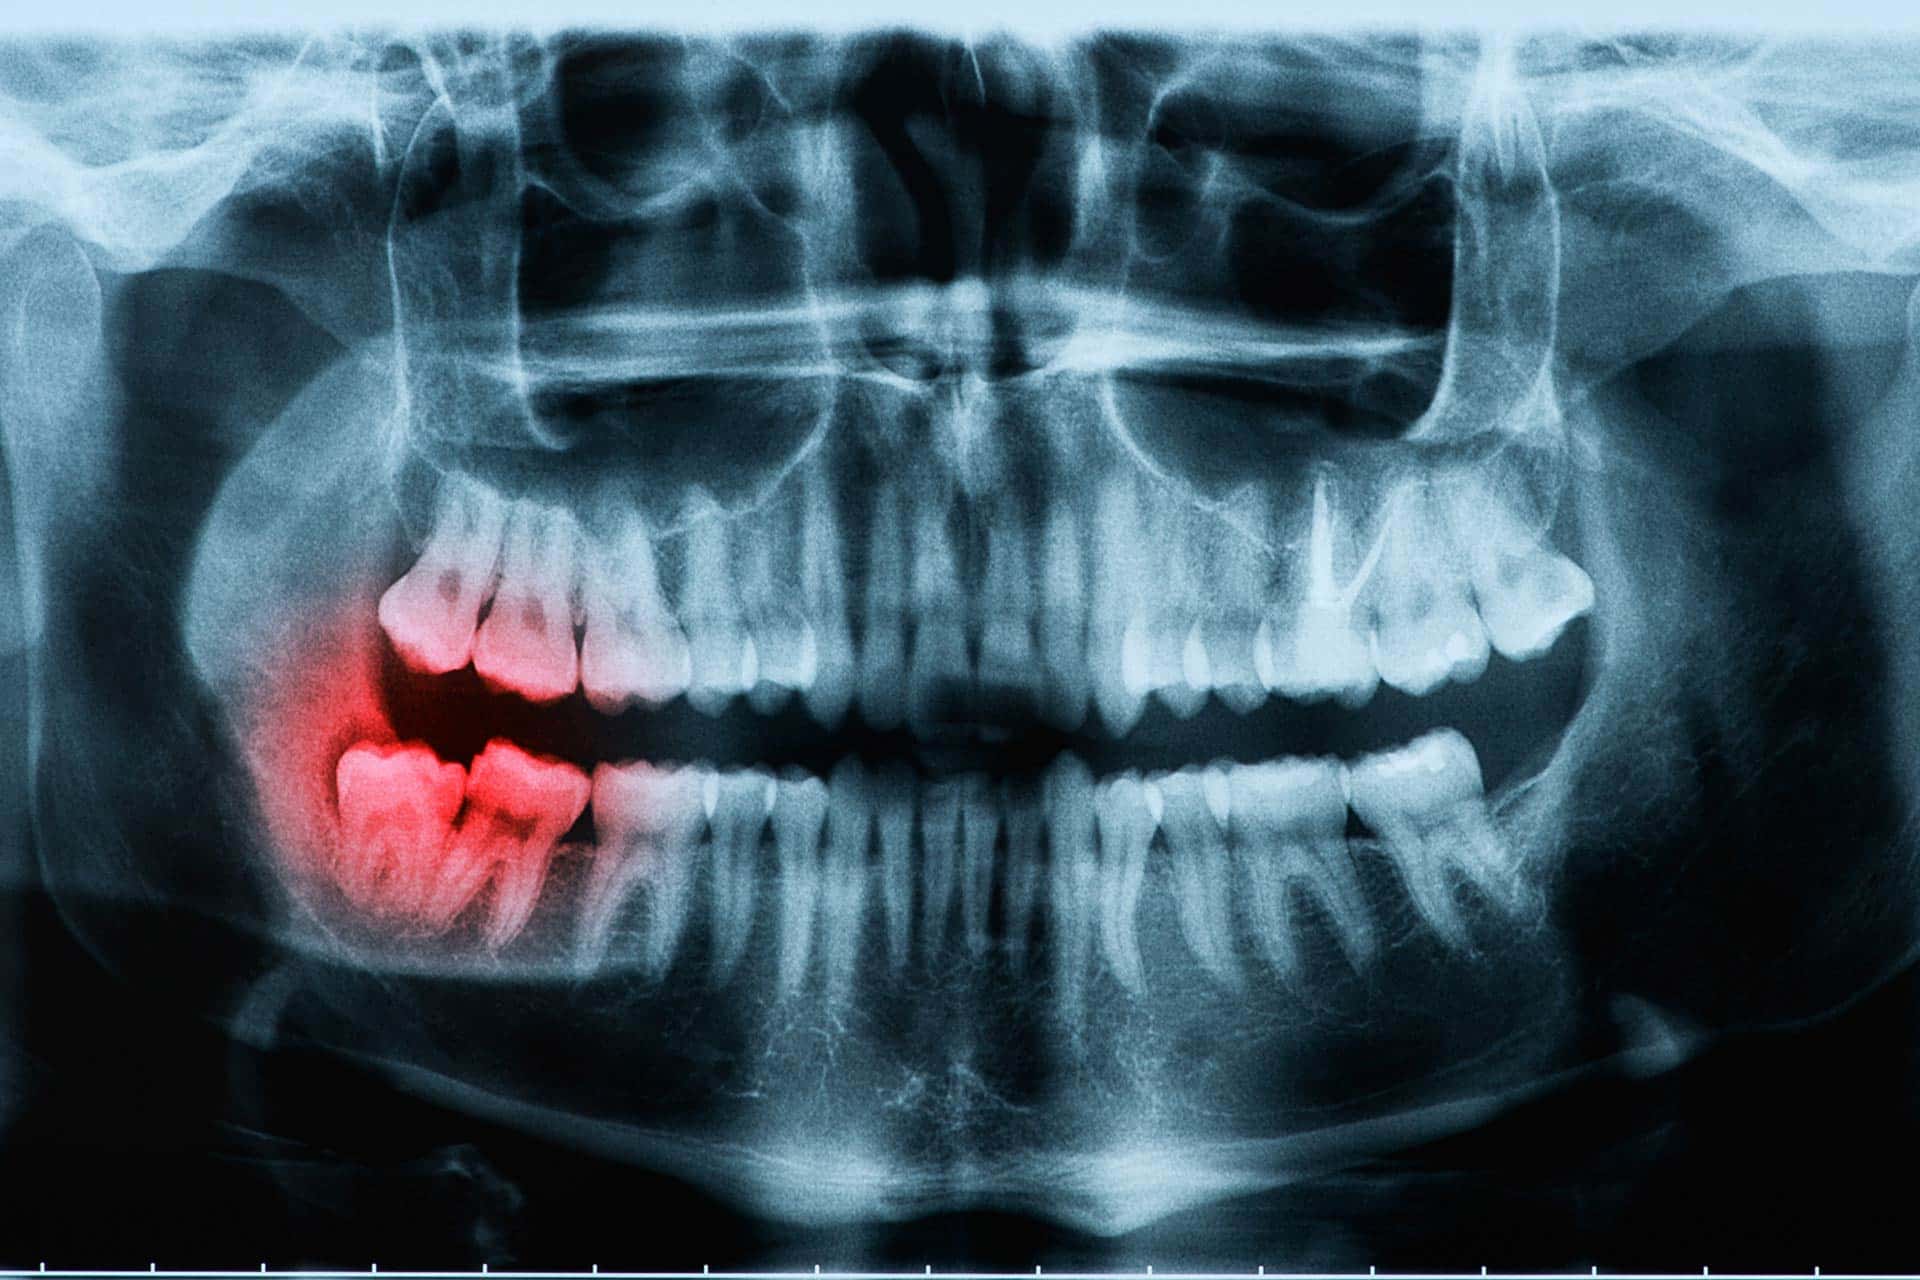

Before you visit an oral surgery center for a wisdom tooth removal your dentist will likely want to start with an oral examination which includes x-rays of your mouth. This is the first step in determining if your wisdom teeth need to be removed. During this visit, your dentist will check the positioning of the wisdom teeth and determine any current or future problems that your wisdom teeth may cause as they continue to grow and move.

Typically your wisdom teeth are first discovered via a dental x-ray in your teenage years, but they may not cause any problems until later in life, or even at all. But it’s best to have them checked at your regular dental visits. This can prevent them from becoming problematic and painful later down the road.

Your wisdom teeth are the third set of molars in the back of your mouth. These molars usually come in between your late teenage years and early 20’s and they’re usually noticed first on dental x-rays during your routine dental checkups.